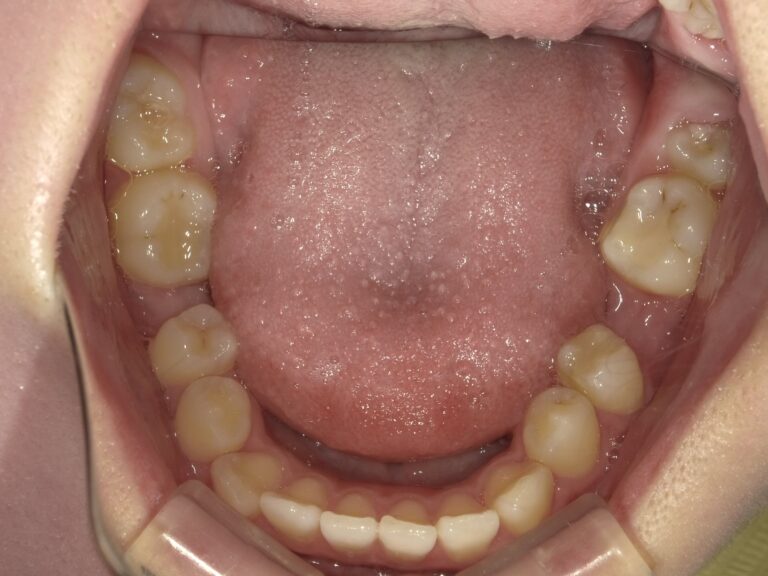

上の前歯には仮歯が入っており、上手くかみ合っていないのと審美的にも良くない状態でした。

前歯の仮歯が壊れて修理してを繰り返していたためか、仮歯表面にざらつきがあり汚れが停滞しやすい状況です。

また、壊れないよう前歯があまり当たっておらず、そのせいか顎の痛みが出てしまい、大きく口が開けられなくなっています。